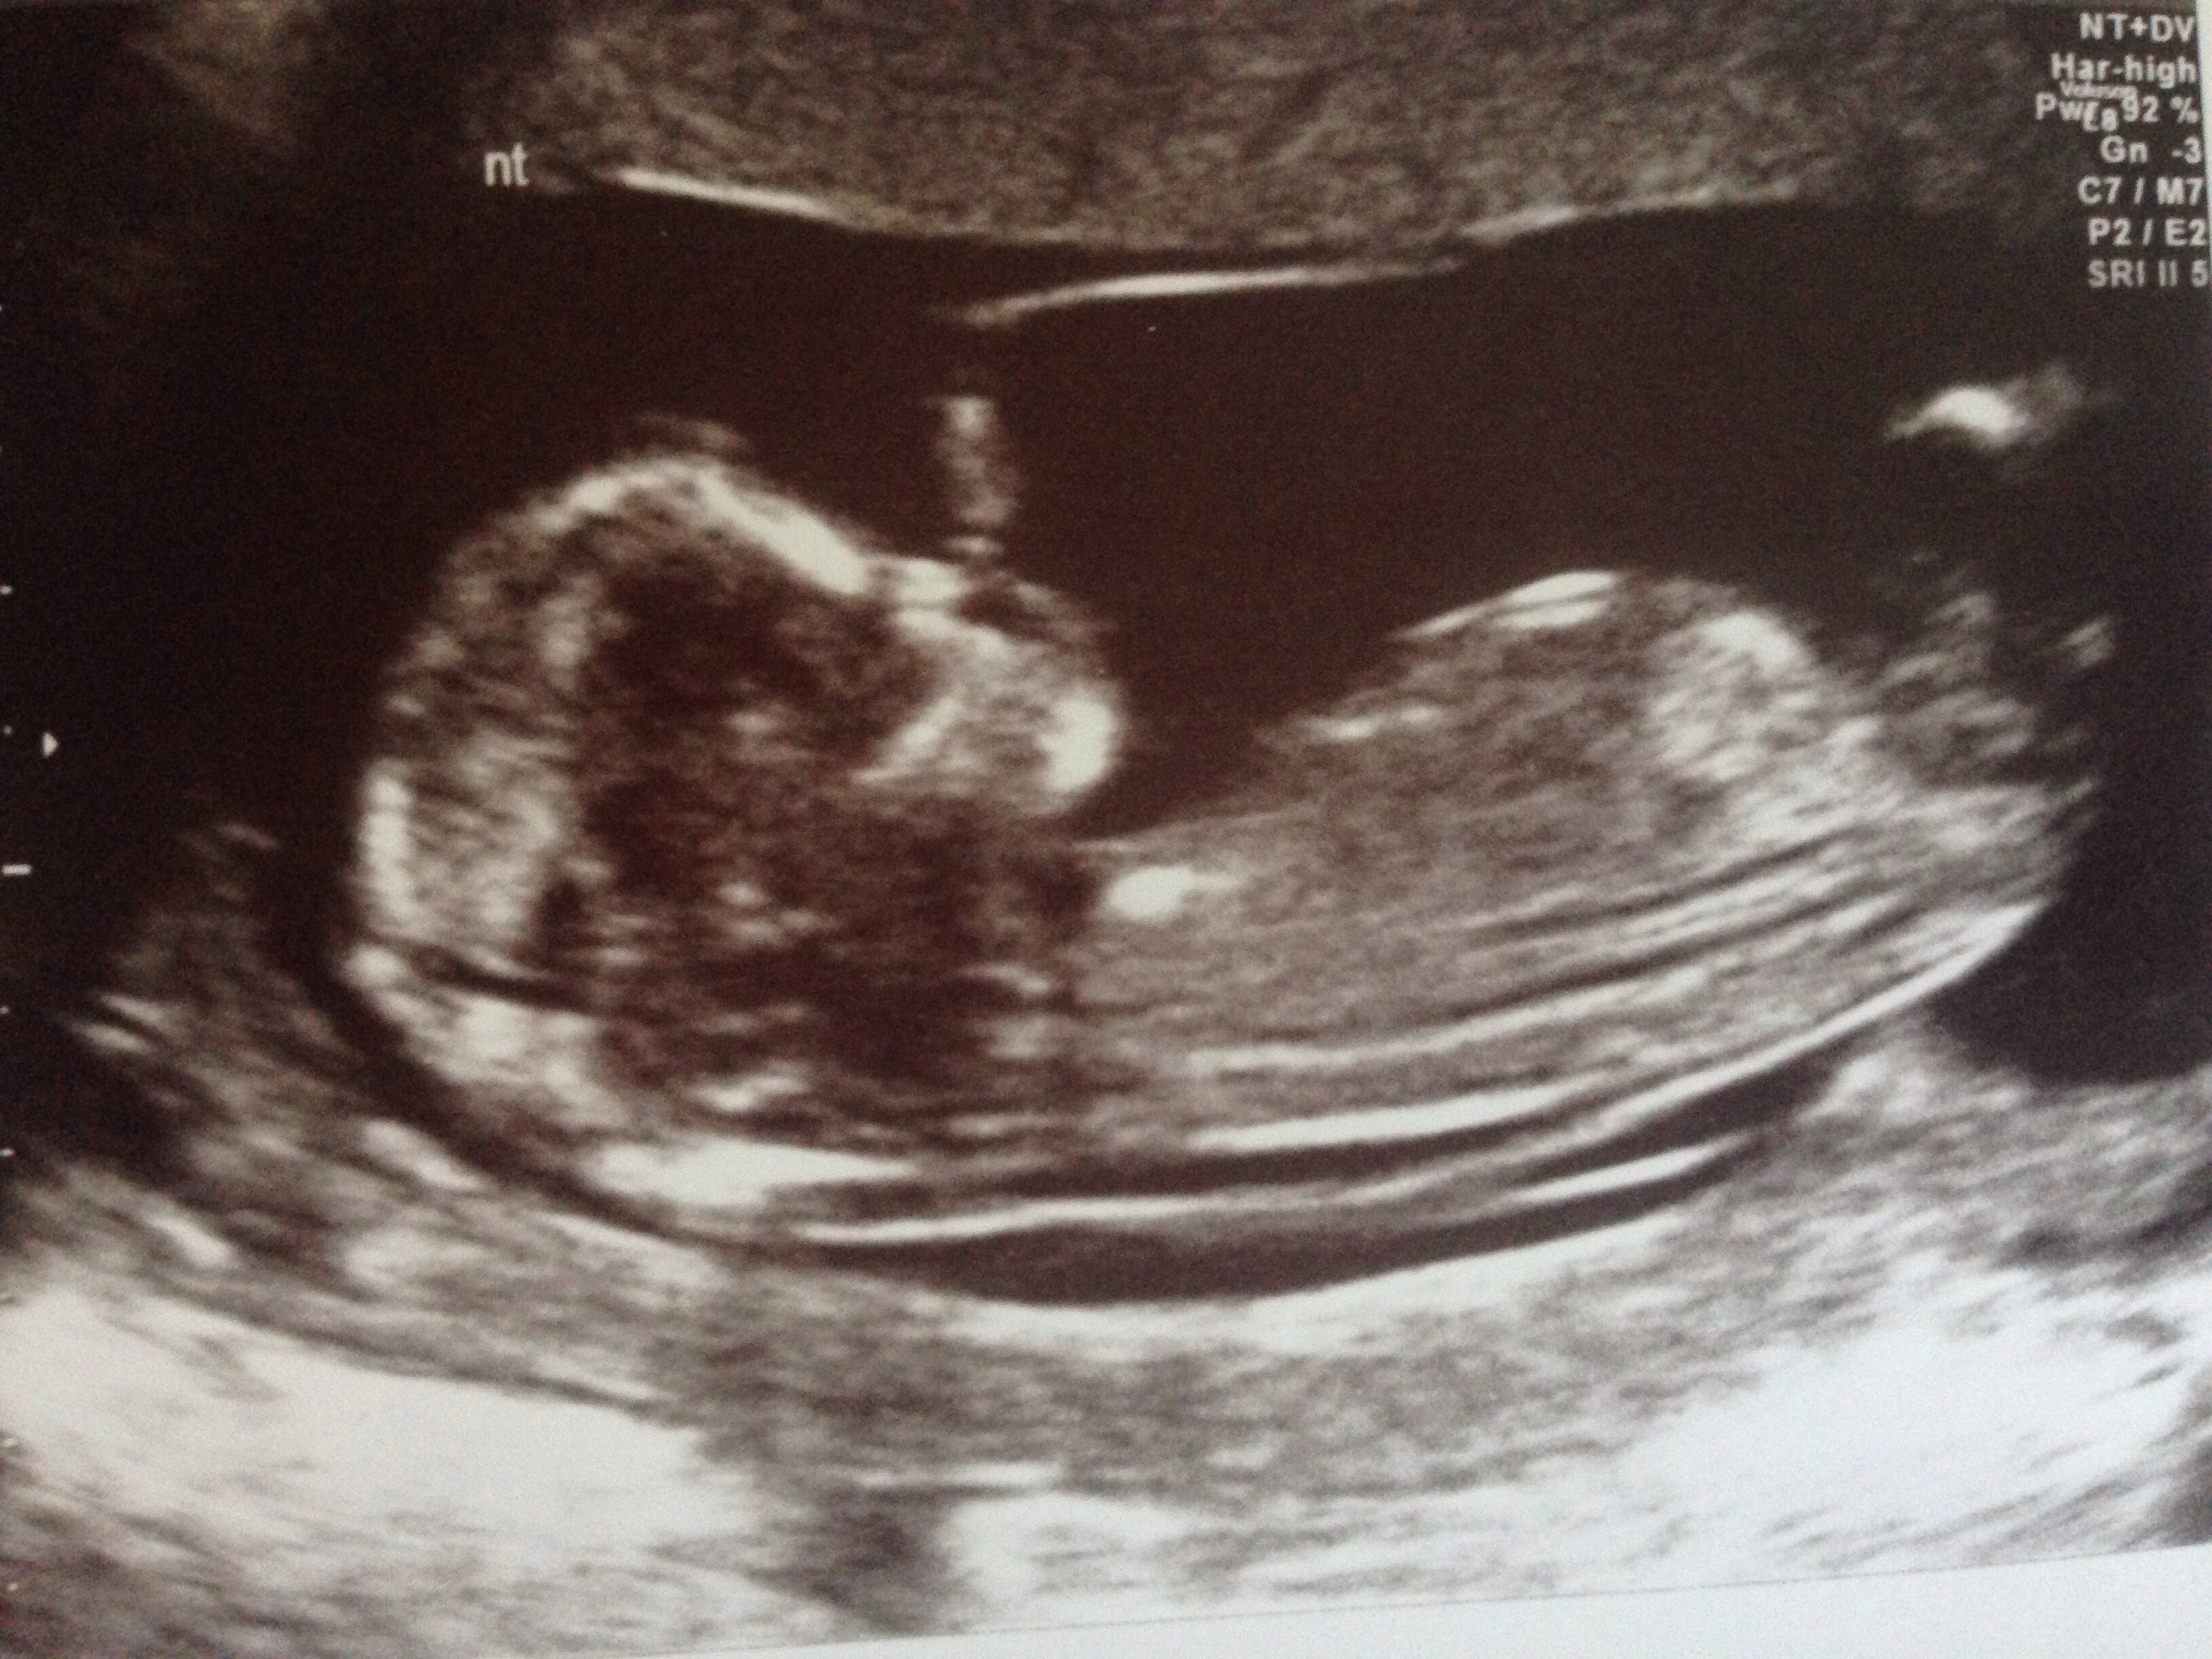

Here are 2 more picturesAttachment 28821Attachment 28822

maybe girl on your second pic.

I would say boy based on secon pic. If that's the nub I think I'm seeing.